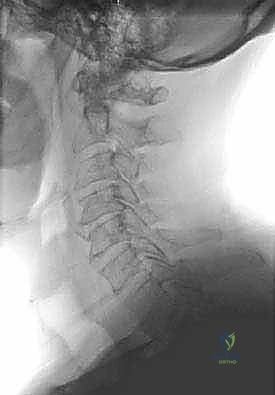

FIG 2 • A. Preoperative lateral cervical spine radiograph demonstrating spondylotic changes: diffuse disc height loss and osteophyte formation.